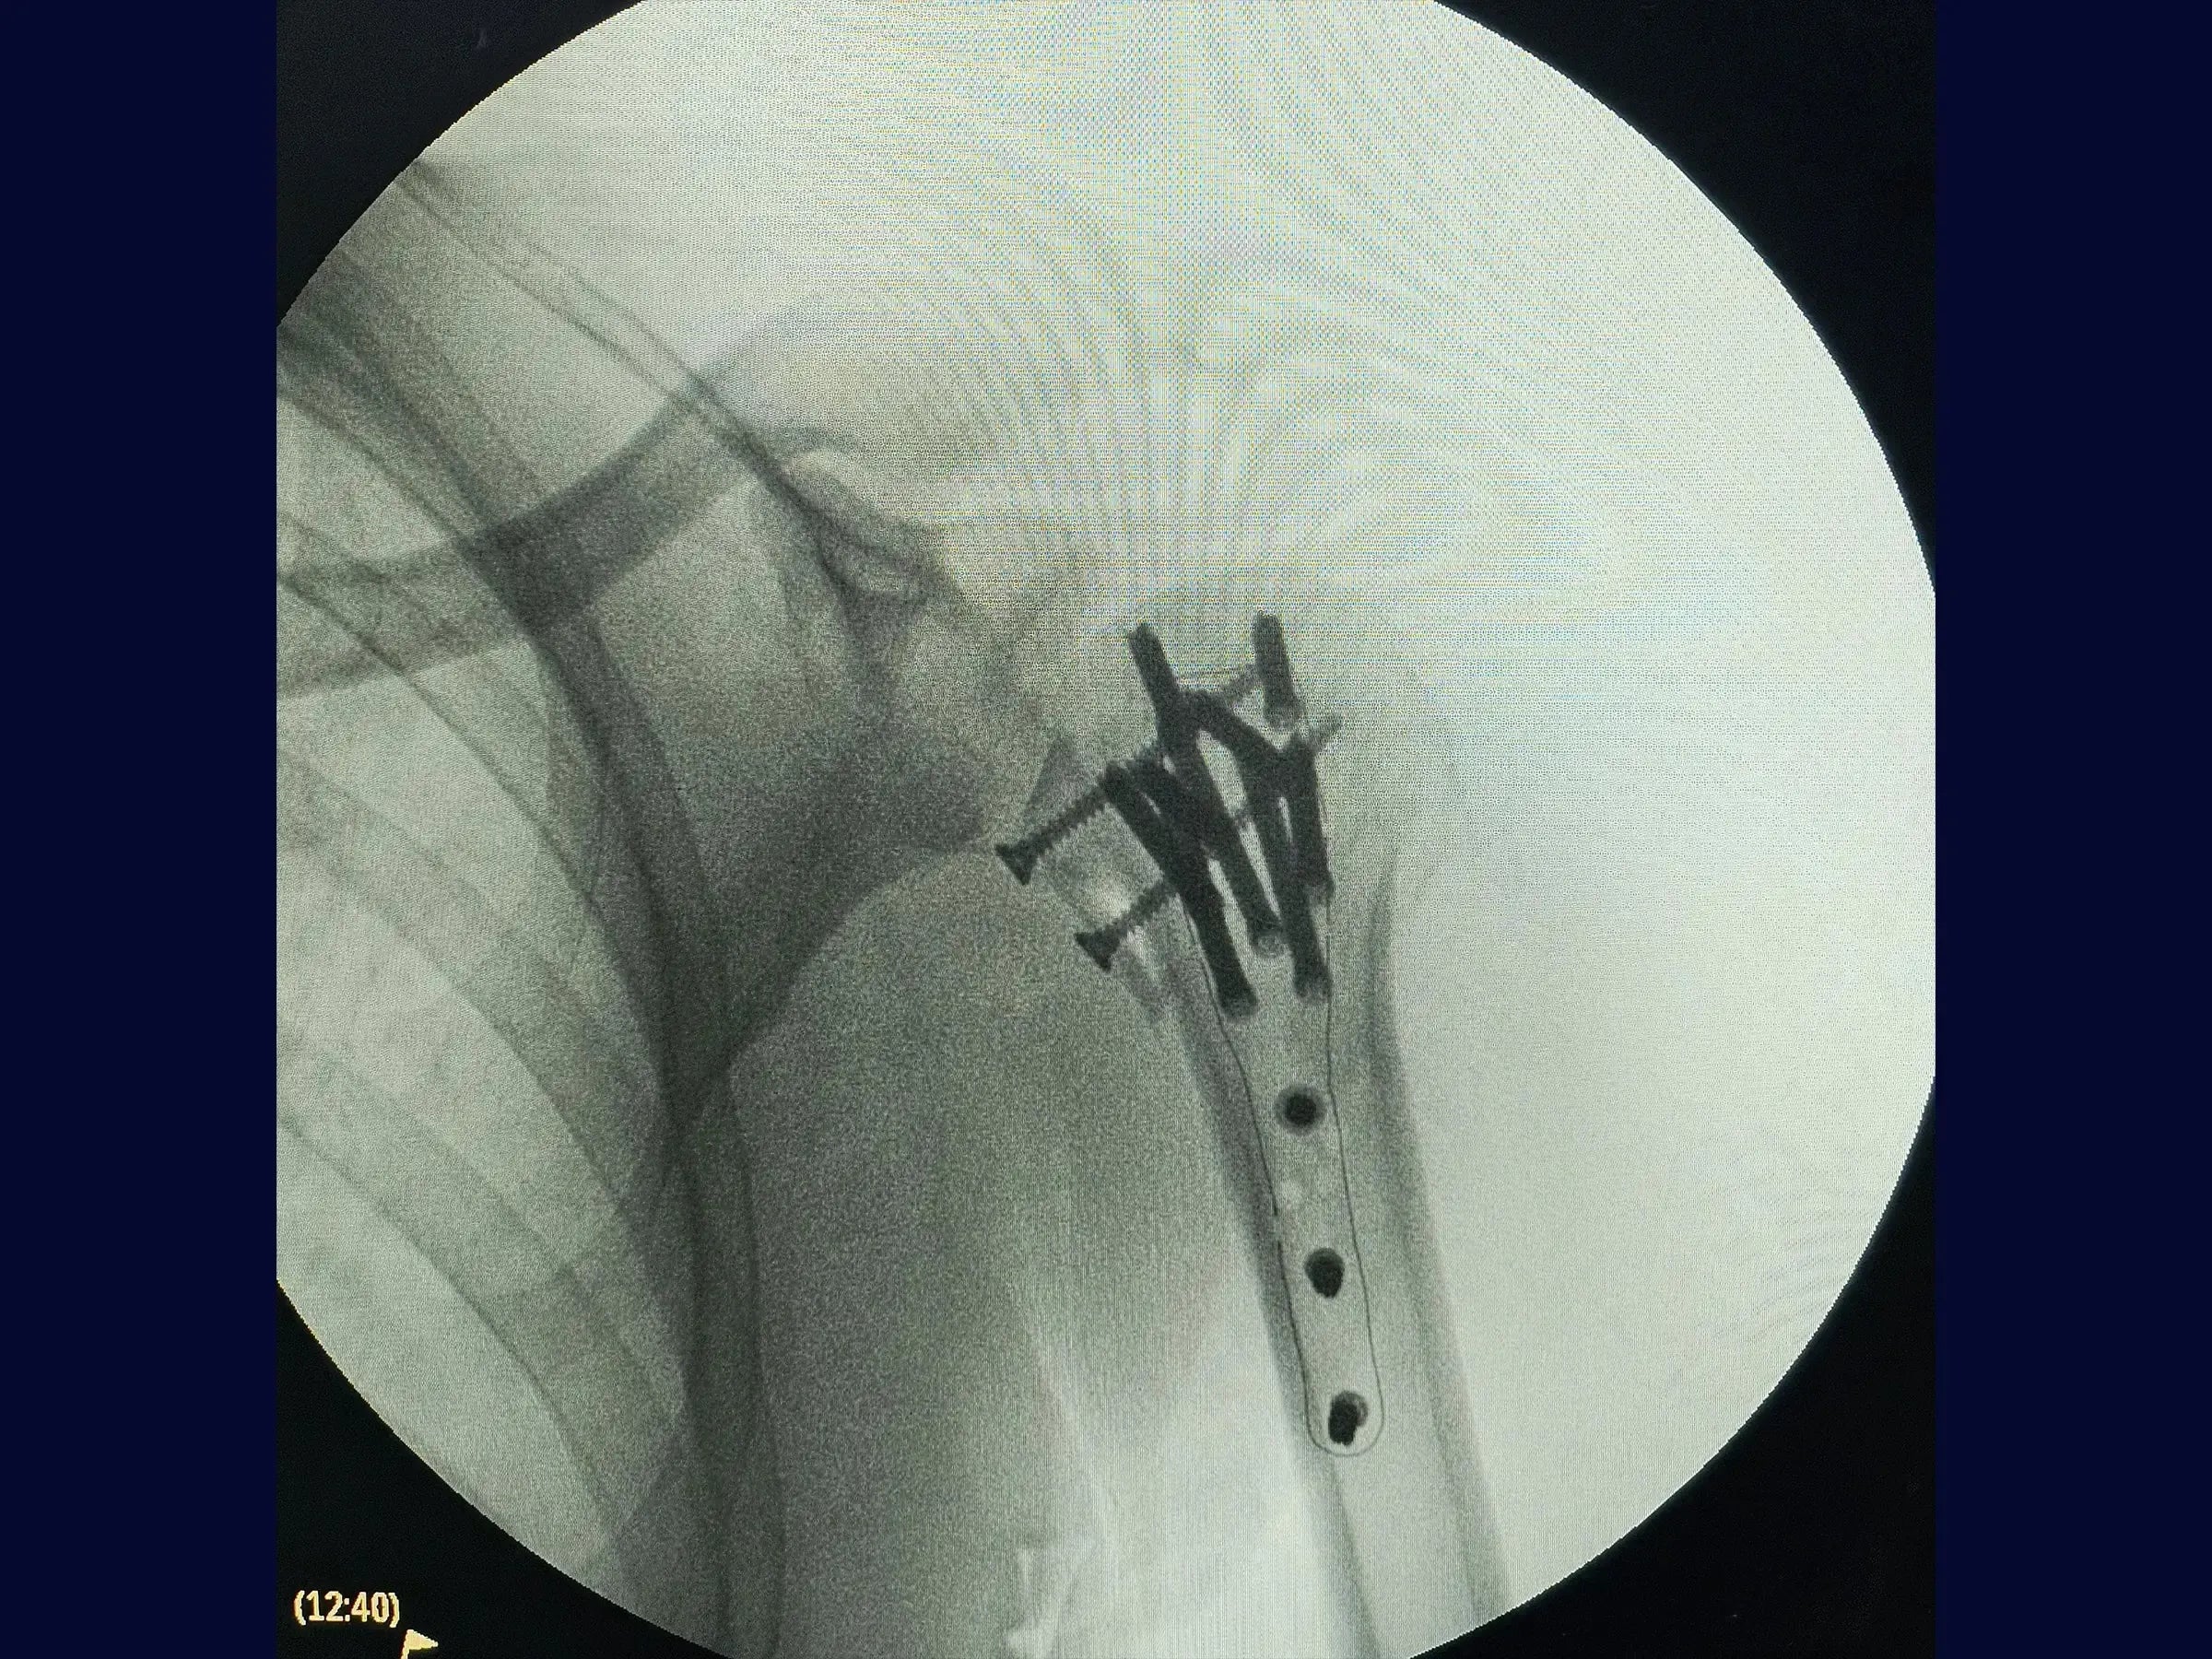

- Fixação com placa de fibra de carbono e parafusos para estabilização de fragmentos.

- Fixação com Placa de Fibra de Carbono: Procedimentos para a amarração do manguito rotador e estabilização da articulação, mesmo diante de fragmentos soltos.

- Manejo de Fragmento da Pequena Tuberosidade: Abordagem para fixação isolada de fragmentos soltos, como a pequena tuberosidade, utilizando parafusos adicionais.

- Posicionamento Anatômico Otimizado: Técnicas para garantir a redução da articulação com posicionamento anatômico e tuberosidades amarradas para um resultado seguro.